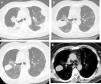

High-resolution chest tomography. (A) before TBCB: bilateral consolidations with peripheral and peribronchovascular air bronchogram. (B) 1 month after TBCB: lesion with air-fluid level in right upper lobe. (C) and (D) 3 months after TBCB: decrease in the size of the lesion with disappearance or reabsorption of the air content and persistence of the bloody content (hematocele).

Our patient was a 55-year-old man, non-smoker, who was referred to our institution for slowly resolving pneumonia. A month earlier, he presented with cough, dyspnea, and bilateral pulmonary opacities. He received empirical antibiotic treatment with amoxicillin-sulbactam and clarithromycin, then piperacillin-tazobactam and finally vancomycin, with no clinical improvement and worsening oxygenation. On admission, he was hypoxemic with an oxygen saturation of 90% breathing room air. The analysis showed no significant results: eosinophil count within normal limits, erythrocyte sedimentation rate 34 mm/h, serology negative for HIV, ANCA and ANA normal, and CPK within normal limits. Chest computed tomography (CT) showed bilateral consolidations, predominantly peripheral, with peribronchovascular distribution and some areas with reversed halo sign (Fig. 1A). We performed bronchoscopy with bronchoalveolar lavage (BAL) and transbronchial biopsy using a 1.9 mm cryoprobe. Five biopsies were obtained from the right upper lobe, 3 in the posterior segment and 2 in the apical segment. The procedure was completed without complications. The pathology study showed characteristic findings of organizing pneumonia. We started treatment with prednisone at a dose of 0.5 mg/kg/day. The patient progressed without fever and his dyspnea improved progressively. One month after treatment, a follow-up chest X-ray showed a cavitary lesion in the upper field of the right hemithorax. A chest CT without contrast agent was performed to characterize the image, revealing a mass with smooth margins, 3 cm in diameter, in the posterior segment of the right upper lobe (Fig. 1B). The patient was asymptomatic, with normal labs and erythrocyte sedimentation rate 5 mm/h; nevertheless, we obtained a BAL specimen from the affected lung segment. Microbiological results were negative and BAL cellularity was normal. The lesion was interpreted as a pneumatocele, caused by the TBCB. We decided to take a watchful waiting approach with clinical follow-up. Two months later, the patient was asymptomatic and CT showed persistence of the cavity with a homogeneous density of 30–40 Hounsfield units, in contact with the pleura and the oblique fissure (Fig. 1C and D).

The lesion was unlikely to have a neoplastic origin, given its morphology, rapid development, and reduced size on follow-up. Its appearance following TBCB and its location in one of the biopsied lung segments suggested that it was a complication of the TBCB. The absence of symptoms, laboratory test changes, and microbiological evidence in BAL, and a favorable clinical course without antibiotic treatment, further ruled out the possibility of a pulmonary abscess. Chest CT showed no pleural effusion and the pulmonary parenchyma surrounding the lesion was normal, so the hypotheses of a phantom tumor following the plane of the fissure or a pulmonary hematoma were therefore rejected. The radiological characteristics of the lesion – air-fluid cavity, thin, regular wall, with smooth margins – supported the diagnosis of pneumatocele. The density of 30–40 Hounsfield units suggested blood in the cavity6 as a secondary complication. In our opinion, the pneumatocele was the product of necrosis generated by the cryobiopsy.